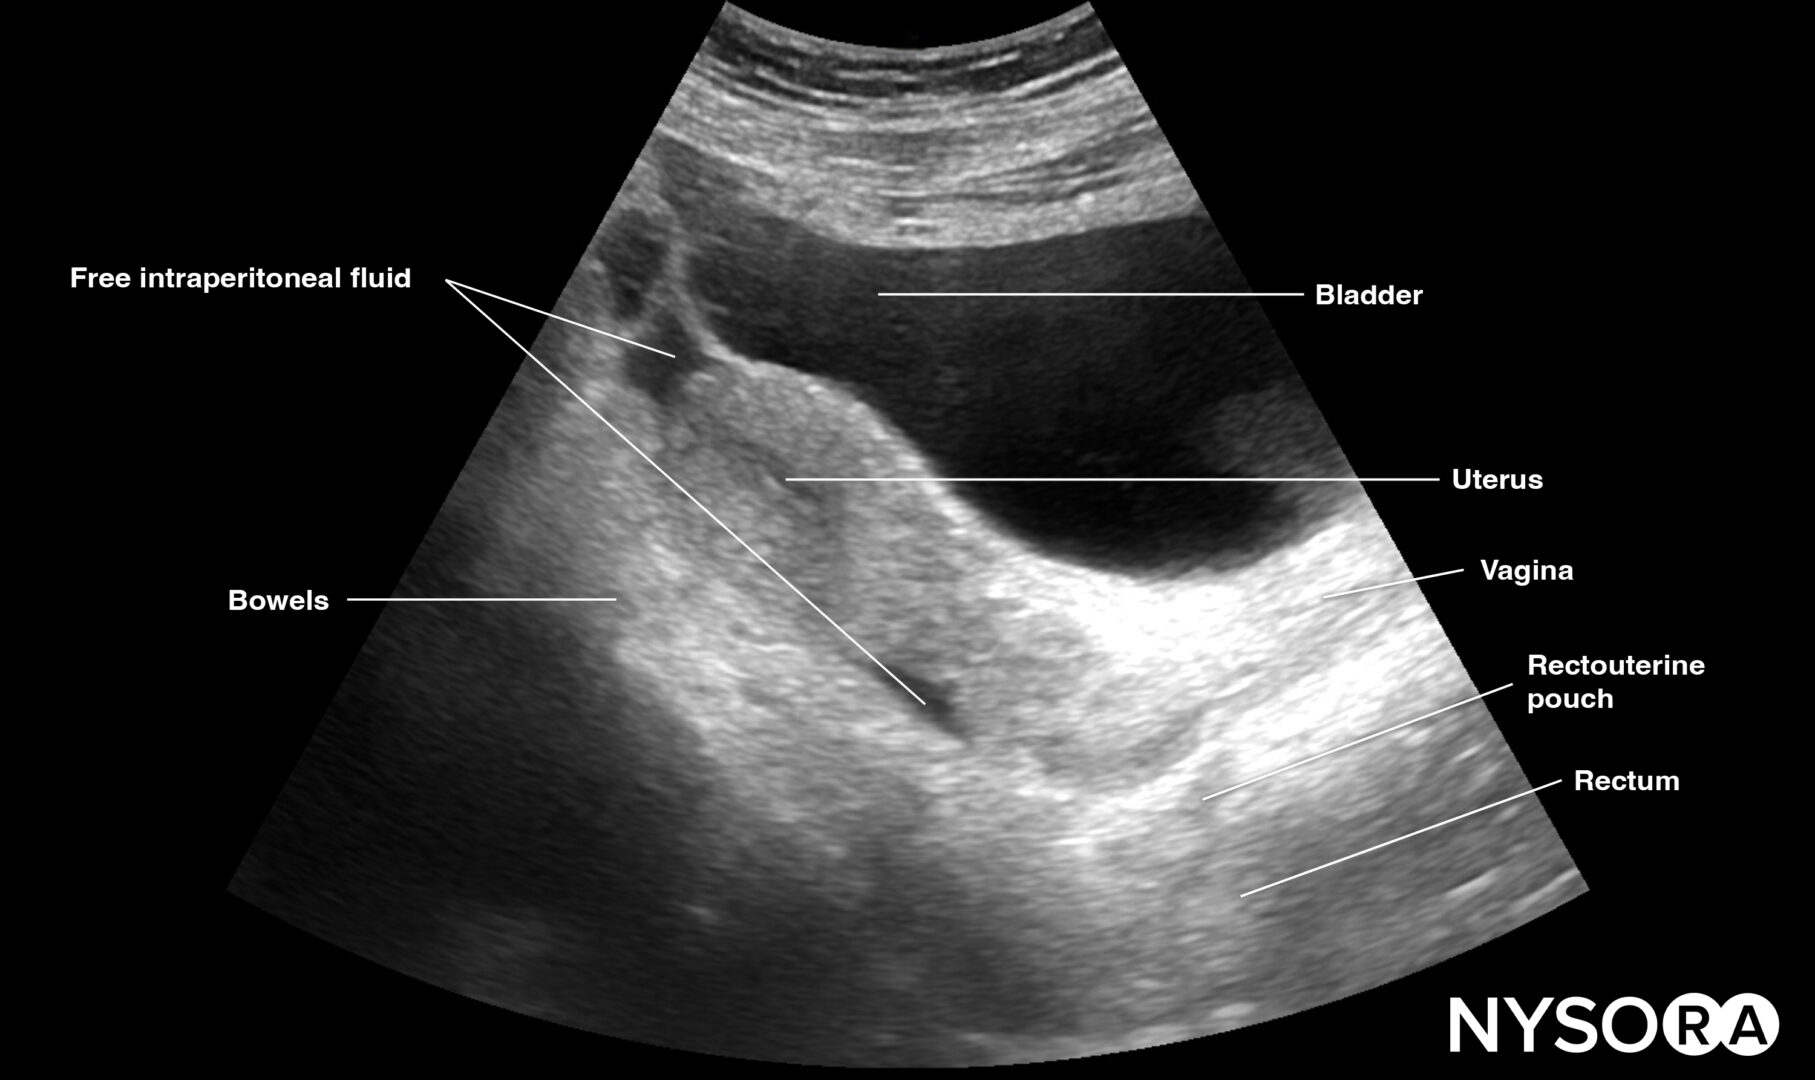

Pelvic free fluid collects behind the bladder or the area lateral to the bladder (rectovesical pouch in men and the rectouterine pouch or pouch of Douglas in women).

Sonoanatomy of interest in females:

Longitudinal view of the female pelvis with free fluid in the rectouterine pouch.